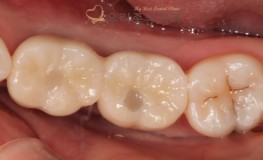

충치치료

우리좋은치과 Crack으로 인한 치아 발치 및 임플란트 식립 (주** 21.03...